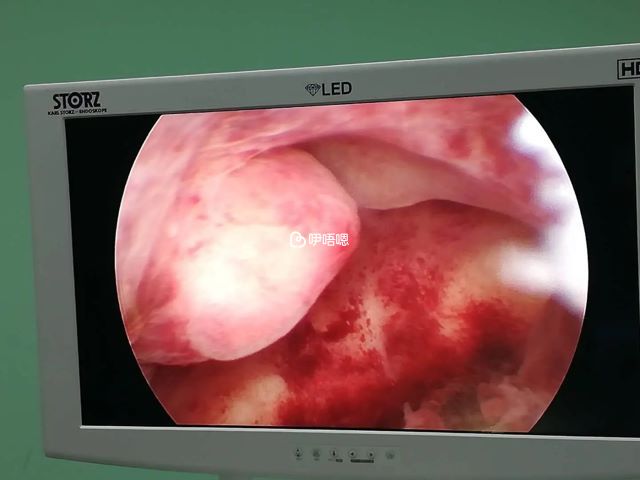

宮腔粘連能治好嗎?宮腔粘連怎麼治療?宮腔粘連治療方法有如下三點,根據不同程度的宮腔粘連患者採用不同的治療方法:

宮腔粘連工具宮腔粘連程度不同,分為輕度、中度、重度宮腔粘連,詳情如下: